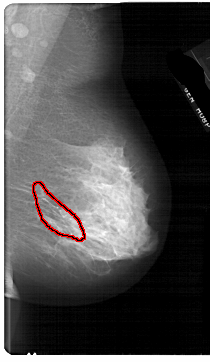

A_1667_1.RIGHT_CC

FILE: A_1667_1.RIGHT_CC.OVERLAY

TOTAL_ABNORMALITIES 1

ABNORMALITY 1

LESION_TYPE CALCIFICATION TYPE FINE_LINEAR_BRANCHING DISTRIBUTION SEGMENTAL

ASSESSMENT 4

SUBTLETY 4

PATHOLOGY MALIGNANT

TOTAL_OUTLINES 1

BOUNDARY